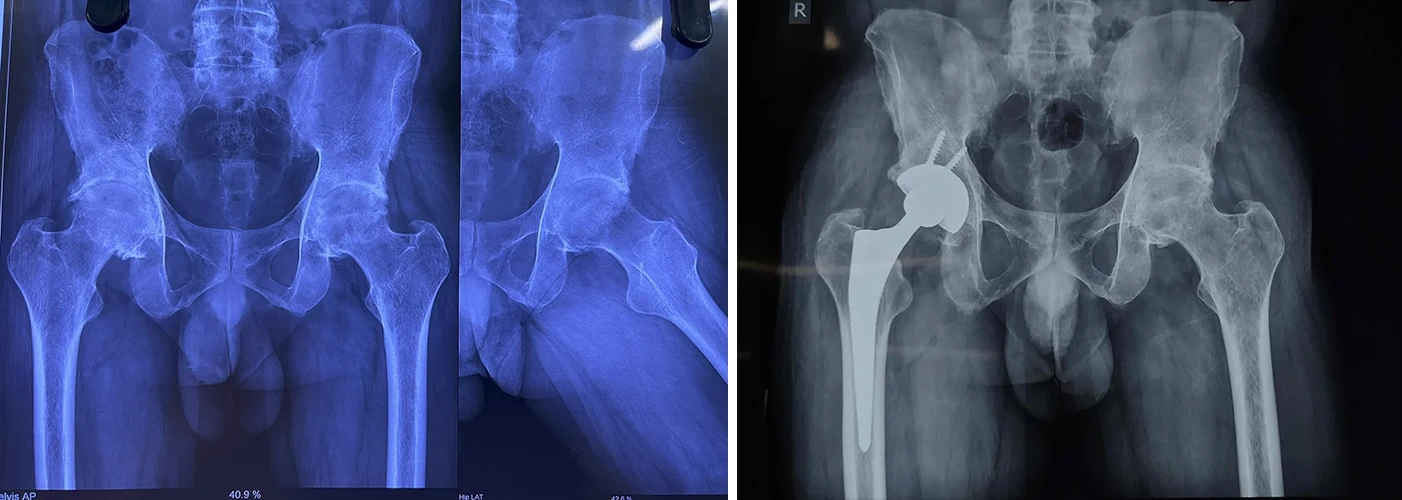

Total Hip Replacement

Are your hips causing you constant discomfort? If you're tired of living with hip pain, Dr. Prasun Sanyal is your best solution.